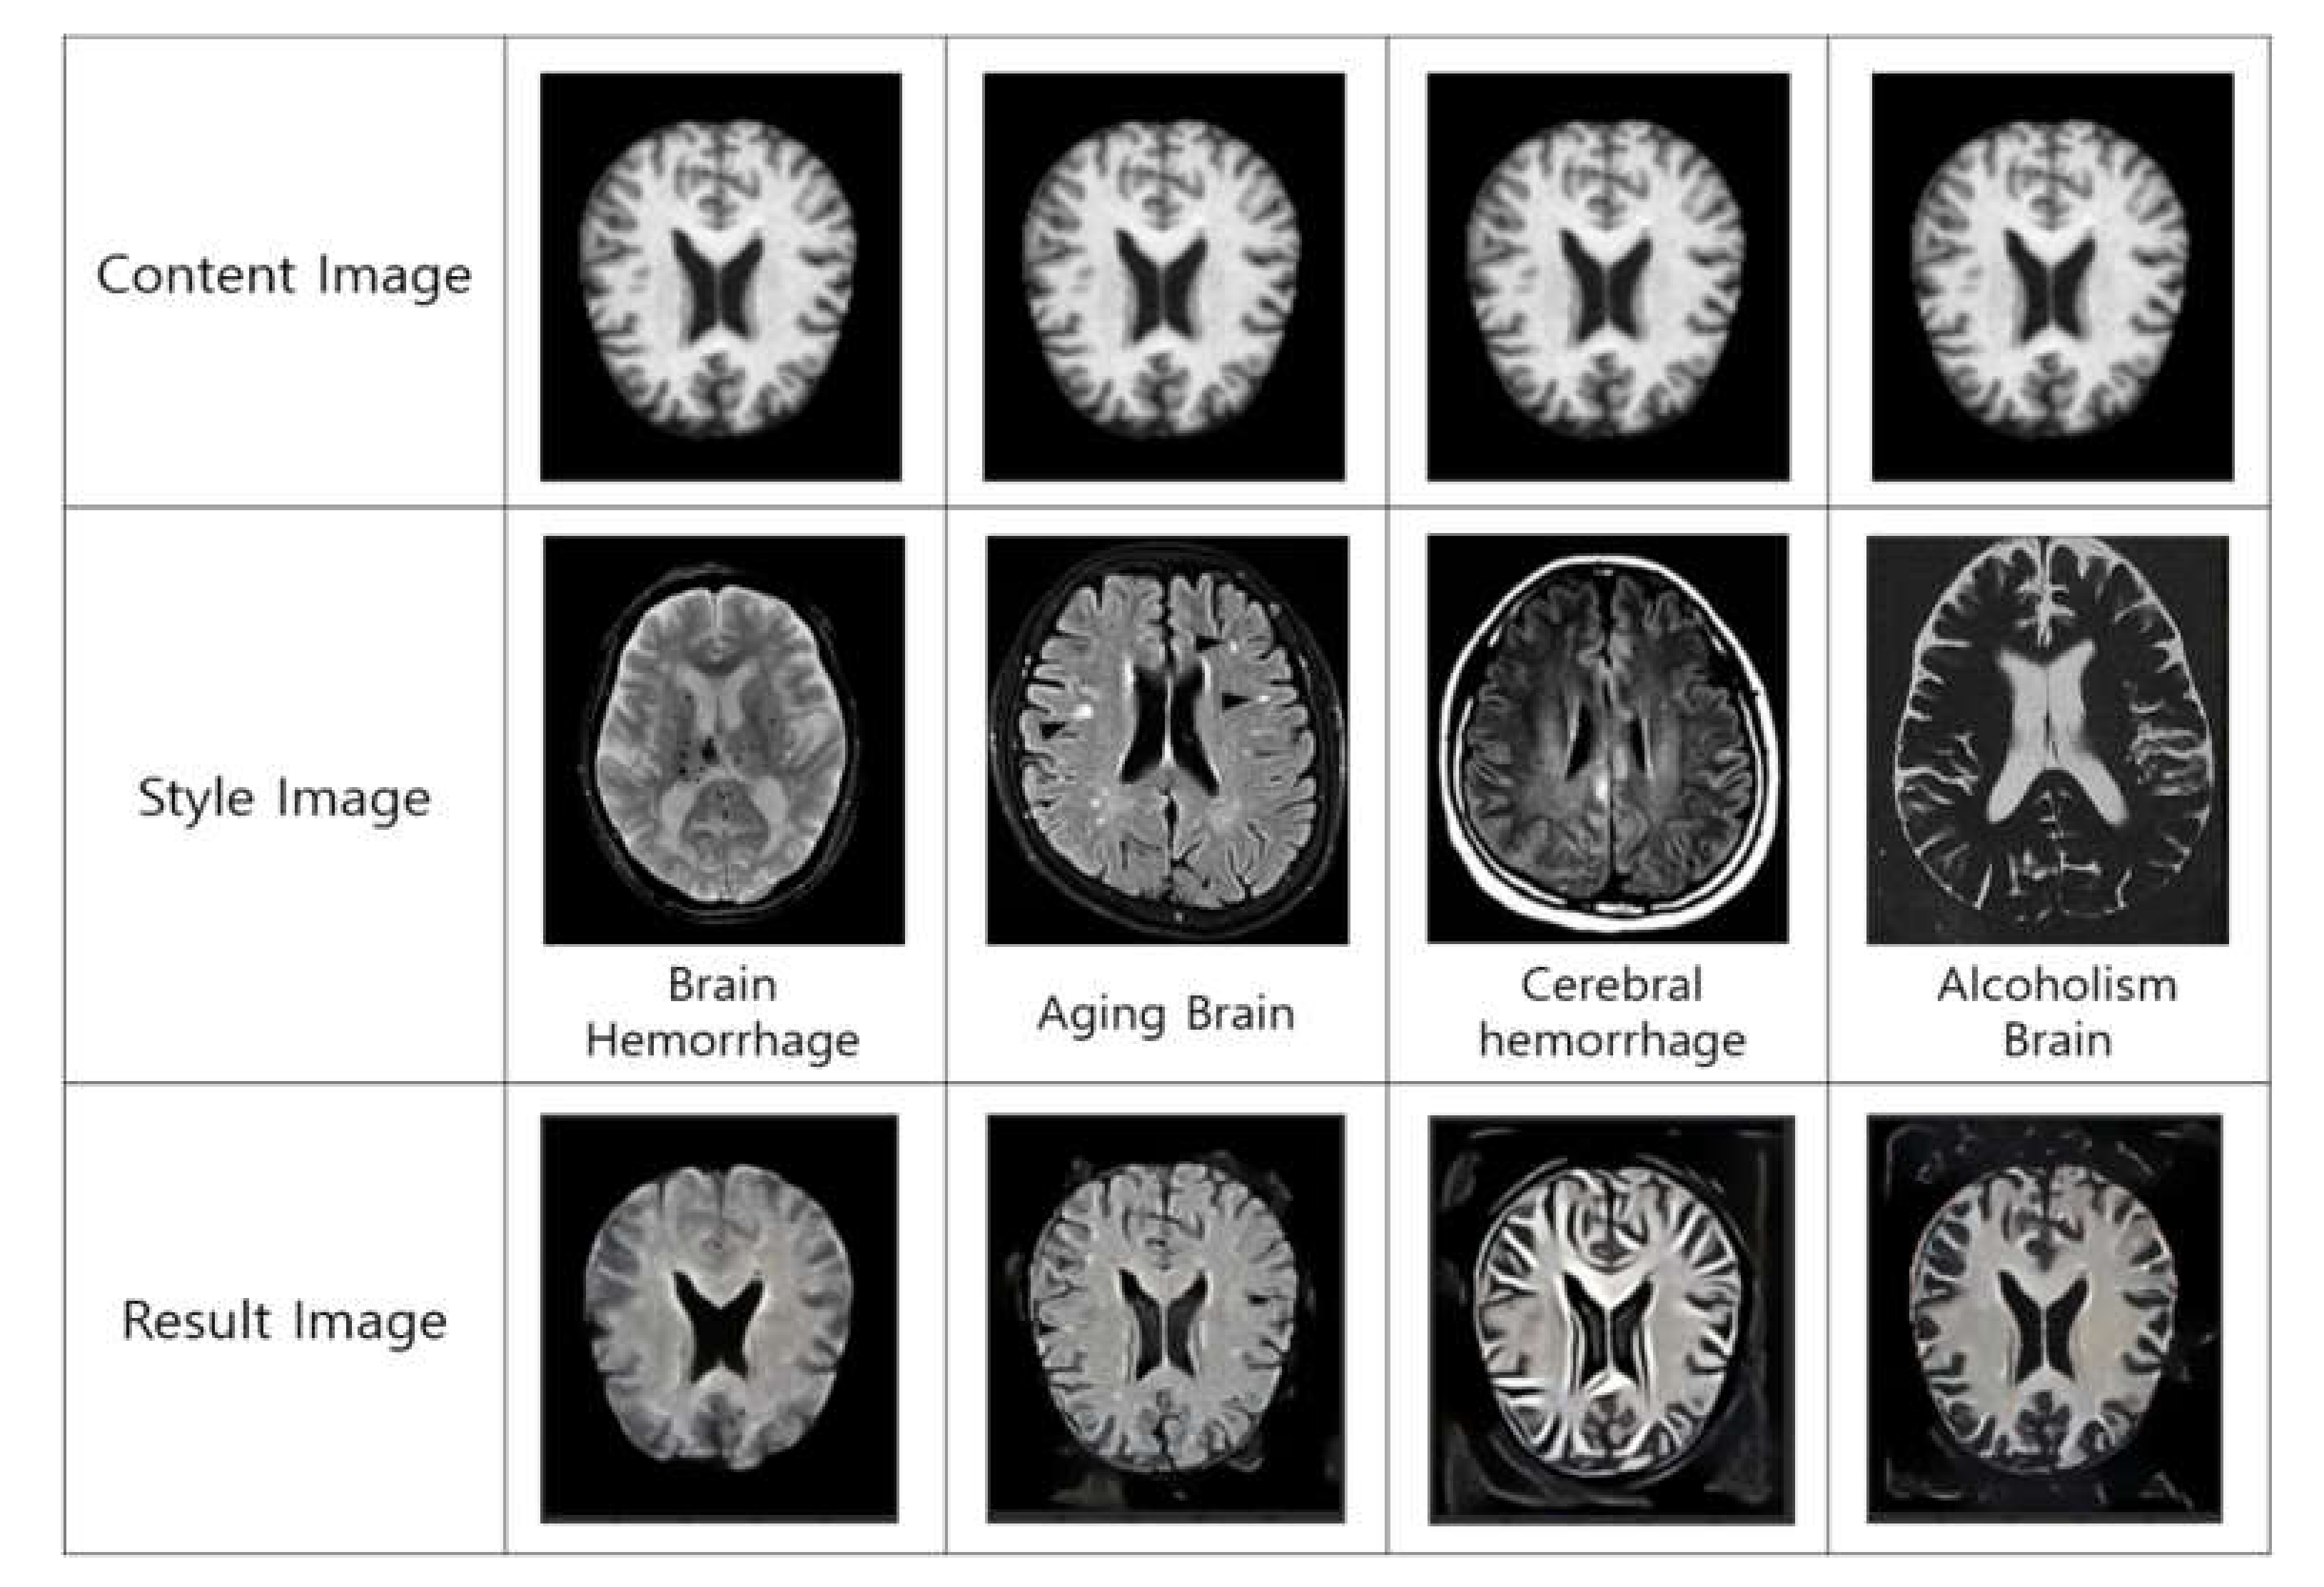

- Image style transfer is a method for transforming image style by keeping the main form of the image using two-image data in the computer vision and, additionally, applying the desired style. Through this, changes in the brain are predicted by transferring the factors affecting dementia.

- Since the background of the image was not removed in the existing method, unnecessary attributes were applied to the image style transmission. In order to solve this problem, the ‘existing method+background removal’ removes unnecessary attributes, but the performance is evaluated poorly because differentiated weights are not applied in each step. However, the proposed method has a different weight and reduces the amount of computation by removing the background in order to prevent unnecessary attribute style transmission, so the performance is evaluated well.